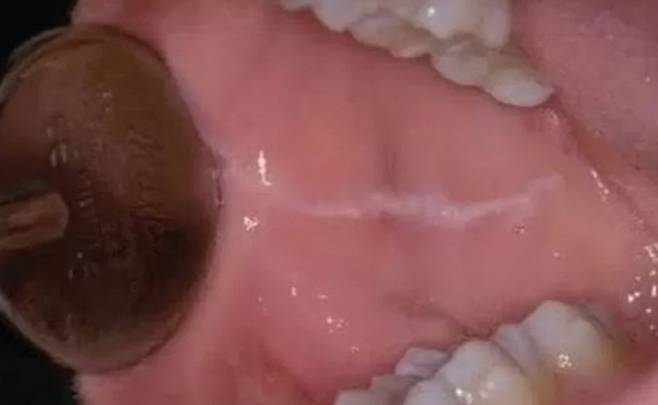

부드럽고 매끈한 속살은 온데간데없이, 이렇게 볼 안쪽에 하얀 가로줄이 생겨 있을 경우 나의 치아 습관을 한번 돌아보시는 게 좋겠습니다. 이 하얀 줄의 정체는 바로 '백선'. 이를 갈거나, 악물거나, 음식을 먹을 때 볼살을 함께 씹는 습관 등으로 인해 생기는데요.

혹시 '어? 난 가로줄이 아니라 그물 모양으로 나 있는데?' 하는 분이 계시다면 '편평 태선'이라는 염증성 질환일 수 있는데요.

스트레스나, 진통제·당뇨약 등 특정 약물의 부작용으로 인해 100명 중 1명꼴로 나타나는 흔한 질환이지만, 심하면 구강암으로 번질 수도 있다고 하니 꼭! 가까운 구강내과에 찾아가 진단을 받아보시기 바랍니다!